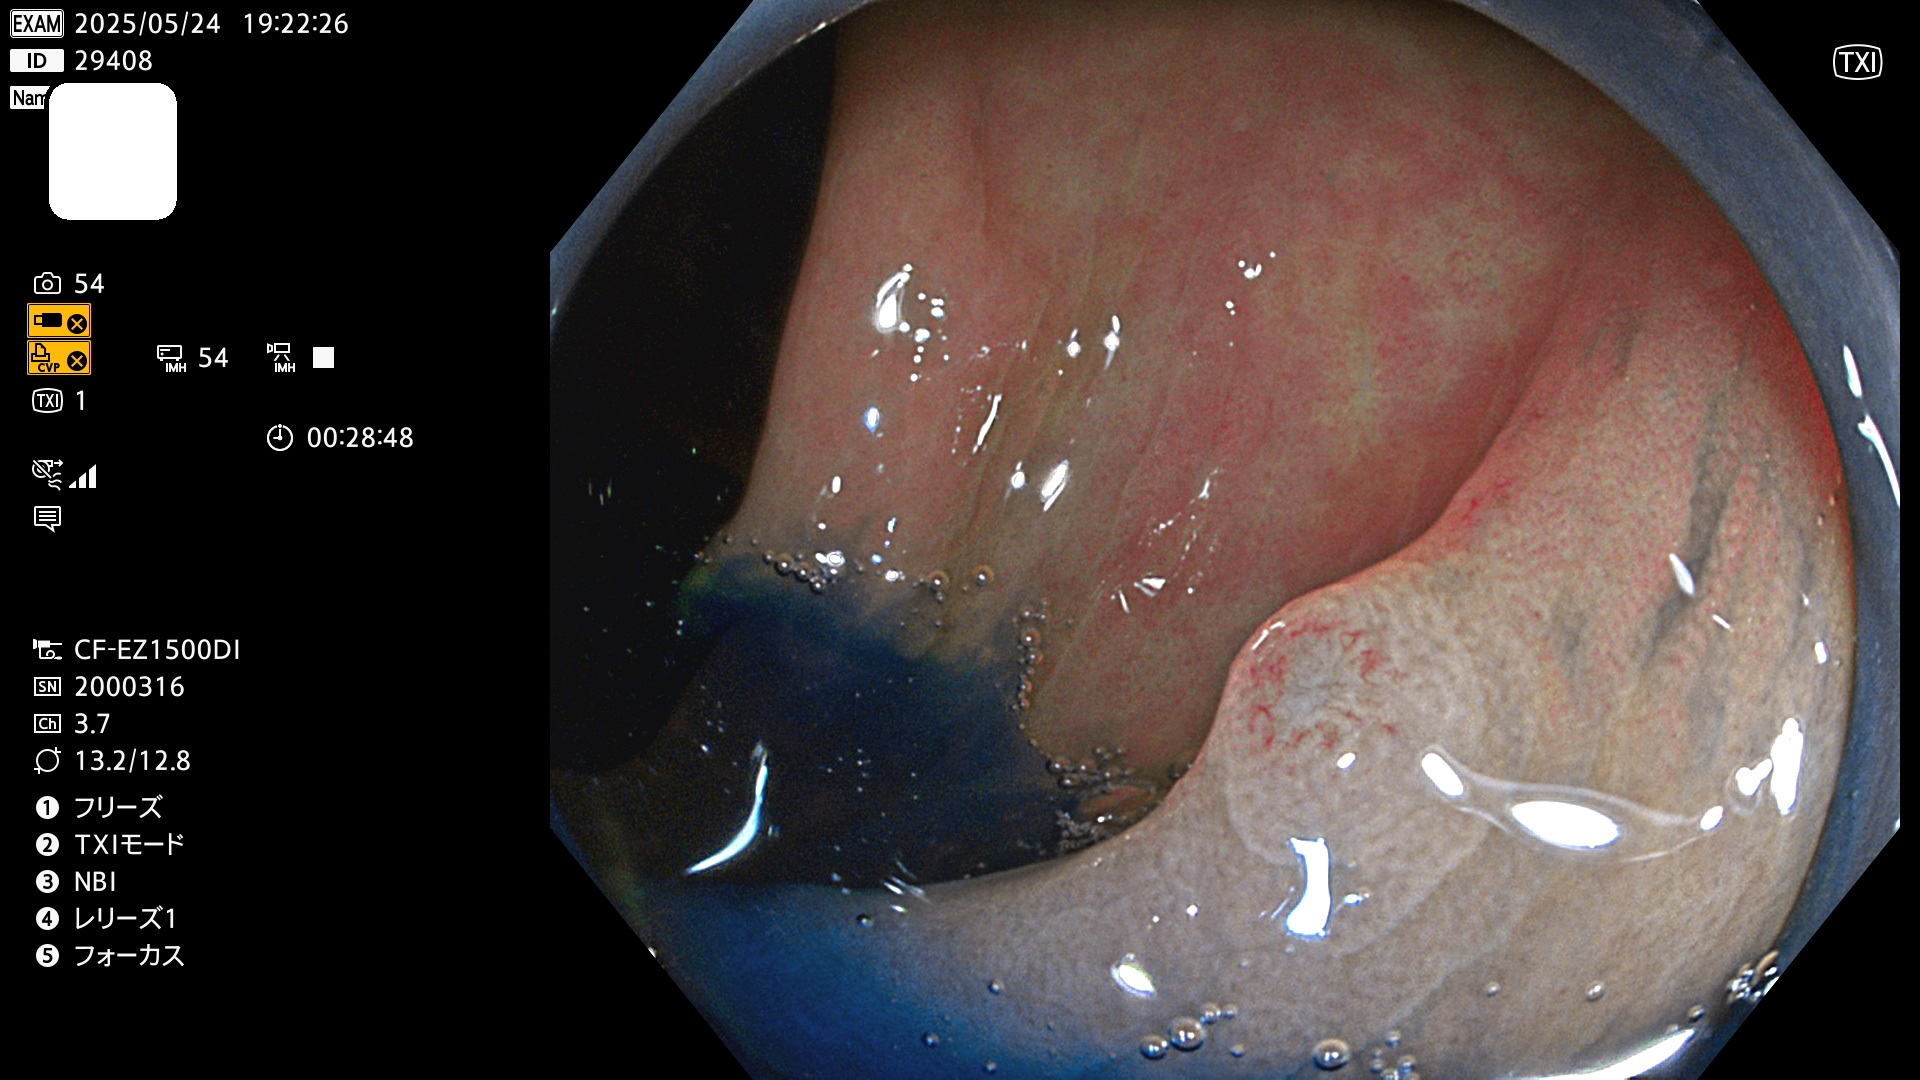

今週のUb、Uc型腺腫

完全に平坦な物をUb、陥凹している物をUcと呼びます。Ubは認識が困難で、Ucはびらん(炎症)と紛らわしいために見落とされやすく、「内視鏡後・大腸癌」の原因になります。

毎週の検査(木・金・土・日)に発見されたUb、Uc型・腺腫を、その週の日曜の夜にUPし1週間、提示します。

抽出の対象期間 2025年5月22日〜5月25日の4日間(48件の検査)10個 (10/48=21%)